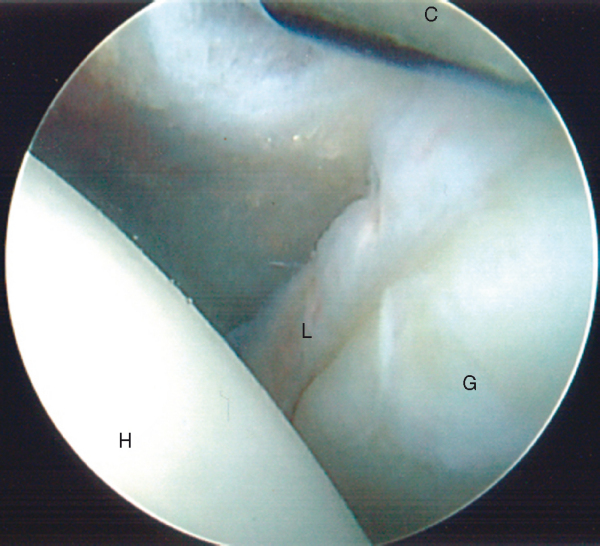

The anterior inferior labrum is evaluated with a probe (

Fig. 1-20

). This area should be inspected for degenerative tearing or scuffing as well as for a true Bankart lesion. In contrast to the anterosuperior labrum, any detachment of the labrum below the equator of the glenoid is considered pathologic. The inferior glenohumeral ligament runs from the glenoid to the anatomic neck of the humerus and can be inspected by externally rotating the shoulder, thereby placing the ligament on tension (

Fig. 1-21

). The humeral attachment can actually be better visualized by placing the scope in the anterior portal.